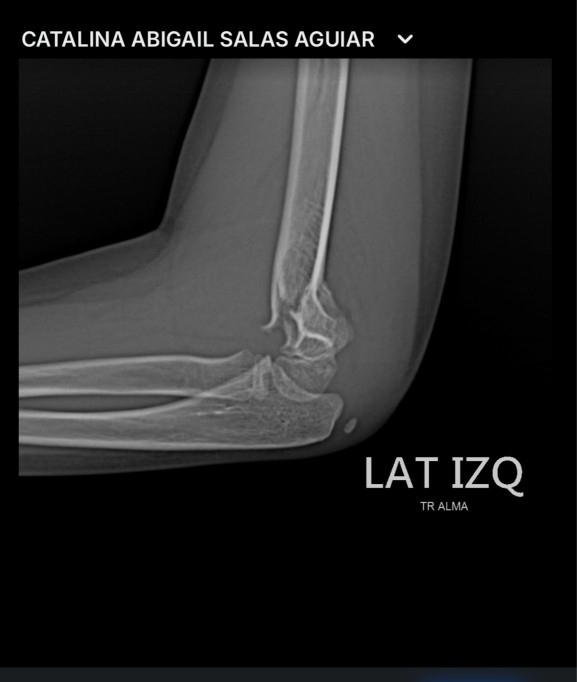

Todo estaba bien hasta que una de sus hijas sufrió una caída que le provocó la fisura en uno de sus codos.

Su hijo tuvo fisura, por lo que fue necesaria una intervención quirúrgica con la colocación de tres clavos en la parte lesionada. Estará hospitalizada hasta su recuperación, por lo que Isidro y su familia pusieron en la Fiscalía General de Yucatán una denuncia para alertar a padres de familia que este lugar, a pesar de ser un establecimiento de diversión extrema, no cuenta con personal calificado, material y primeros auxilios.